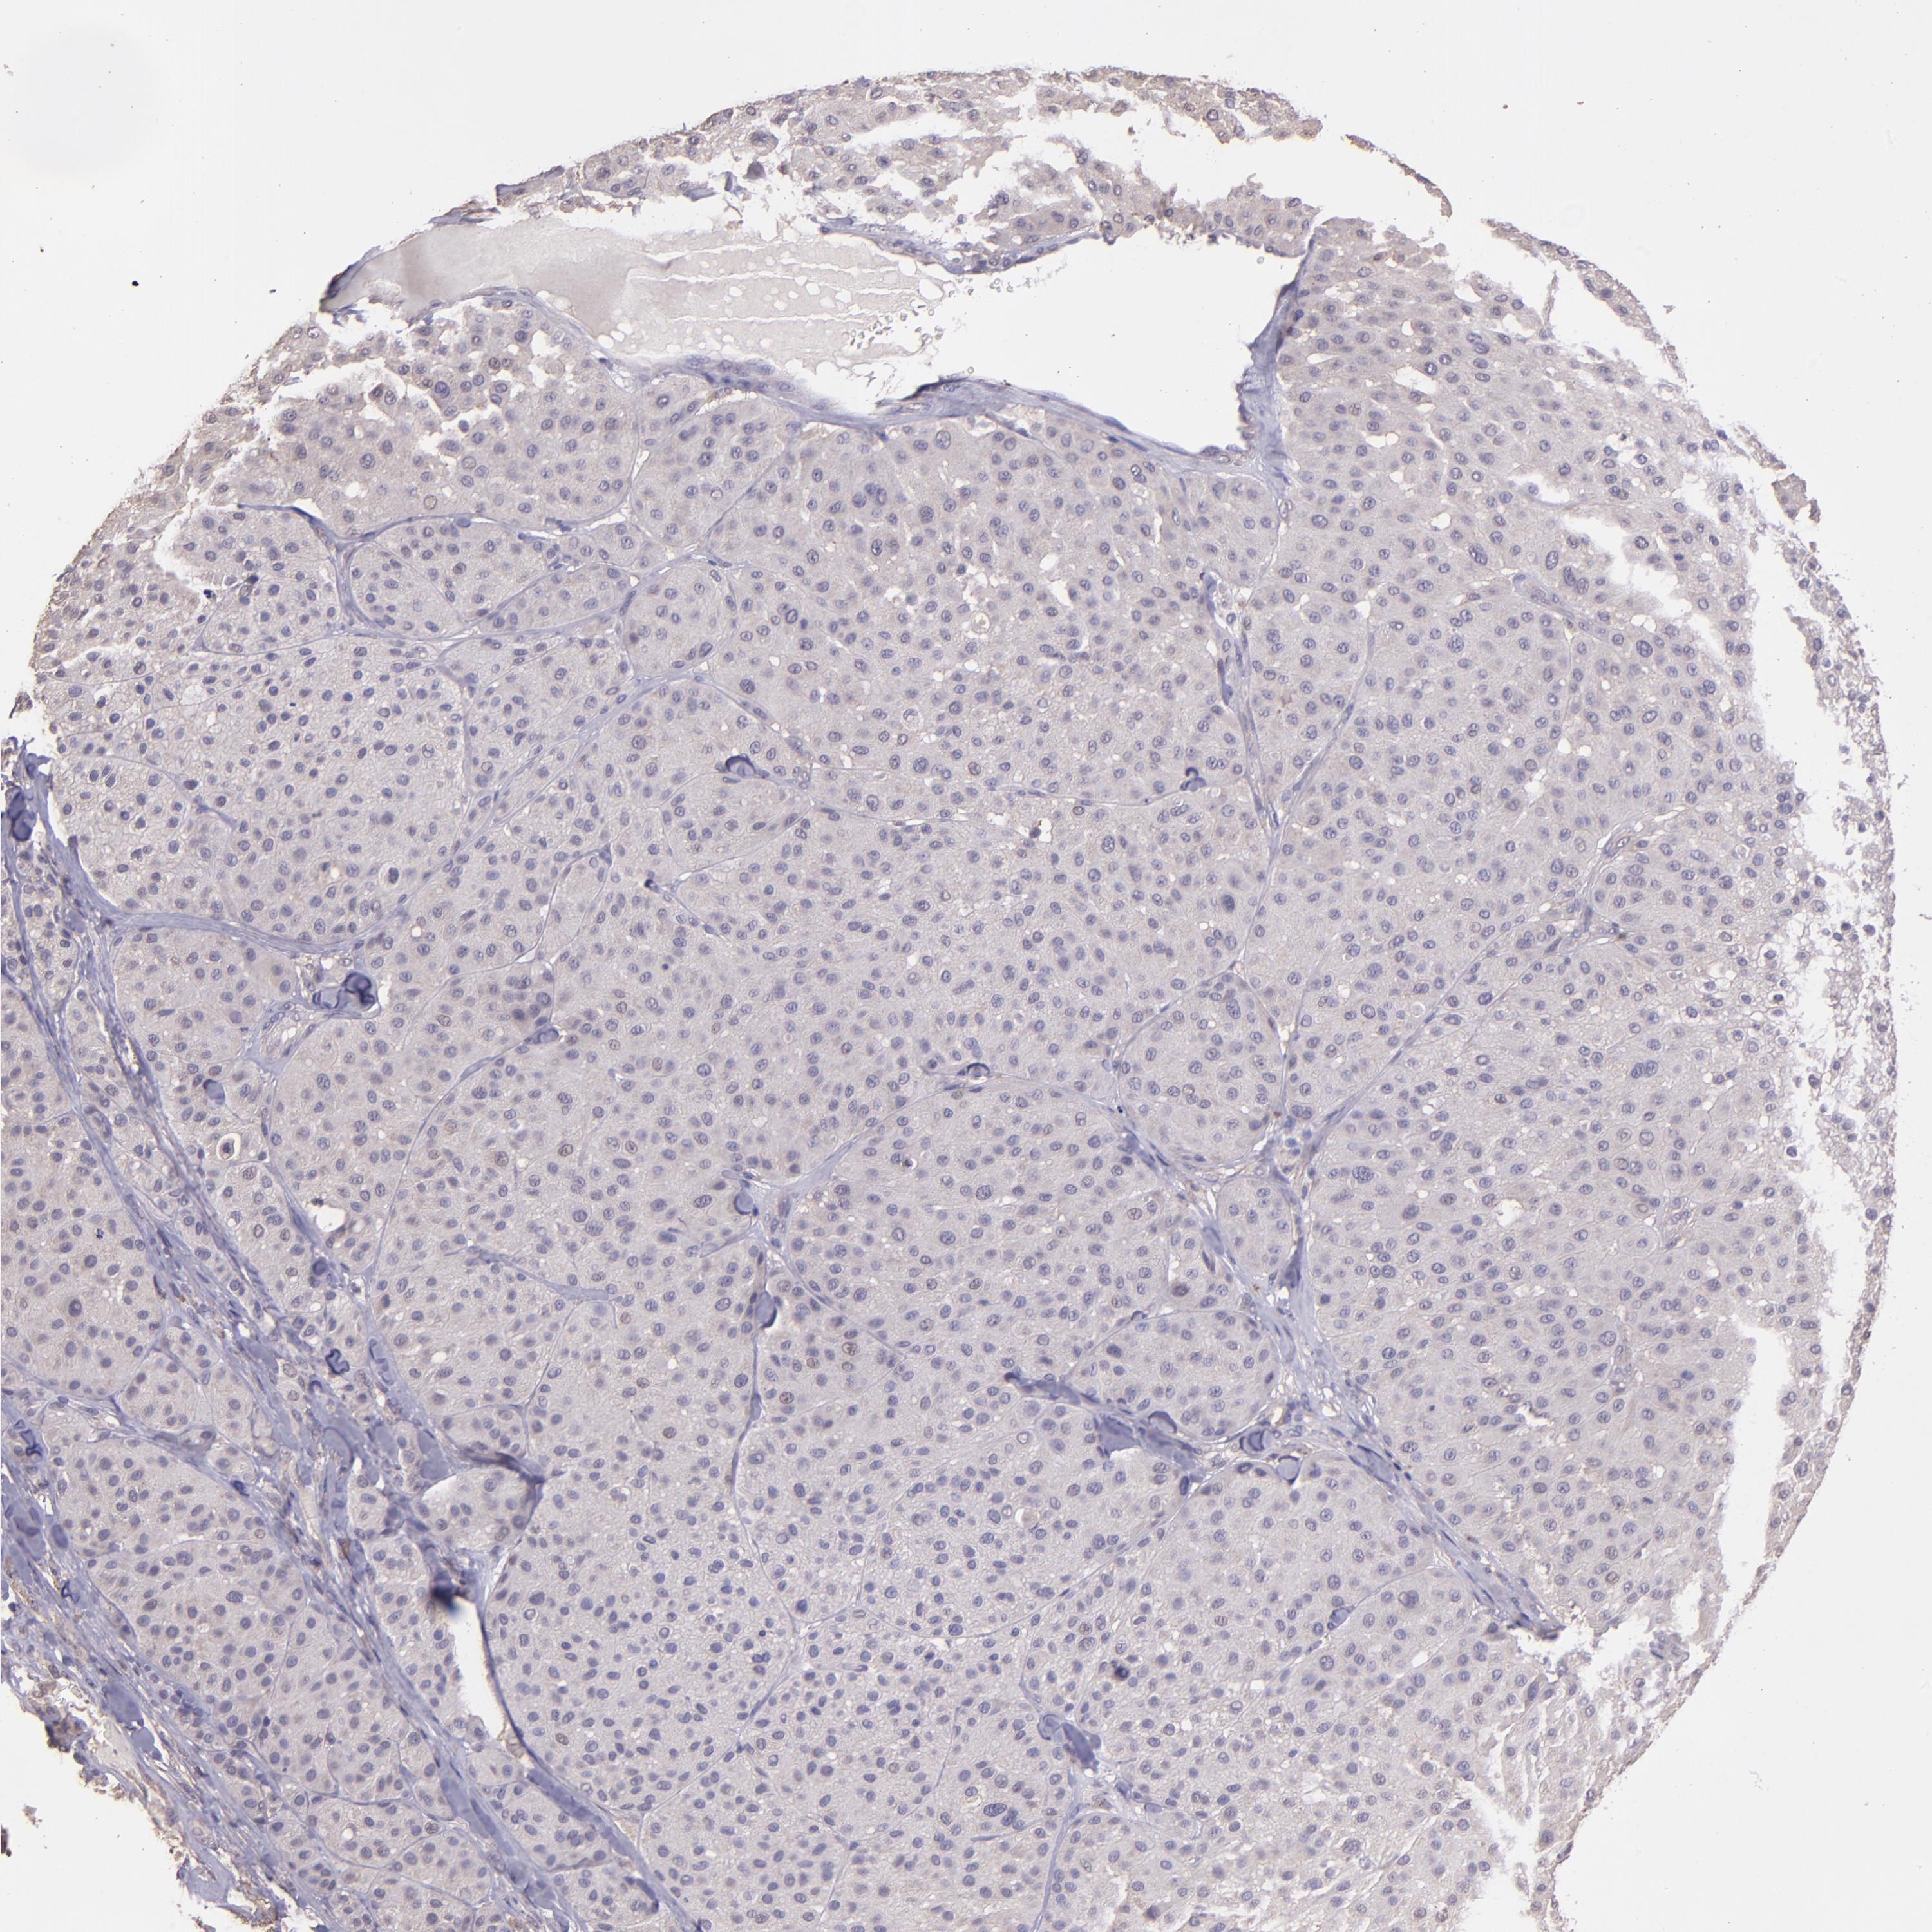

MELANOMA - Protein expressioni

A mouse-over function shows sample information and annotation data. Click on an image to view it in a full screen mode. Samples can be filtered based on level of antibody staining by selecting one or several of the following categories: high, medium, low and not detected. The assay and annotation is described here.

Note that samples used for immunohistochemistry by the Human Protein Atlas do not correspond to samples in the TCGA dataset.

Antibody stainingi

Antibody staining in the annotated cell types in the current human tissue is reported as not detected, low, medium, or high, based on conventional immunohistochemistry profiling in selected tissues. This score is based on the combination of the staining intensity and fraction of stained cells.

Each image is clickable and will lead to virtual microscopy that enables deeper exploration of all samples and also displays staining intensity scores, fraction scores and subcellular localization as well as patient and tissue information for each sample.

Antibody HPA001667

Antibody CAB016724

Malignant melanoma, NOS

Malignant melanoma, Metastatic site